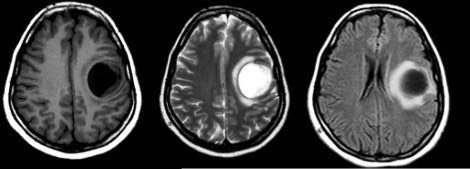

3810. Ребенку 12 лет с жалобами на головную боль, тошноту и судороги выполнена магнитно-резонансная томография, заболеванием, с которым необходимо дифференцировать выявленную рентгенологическую картину, считают